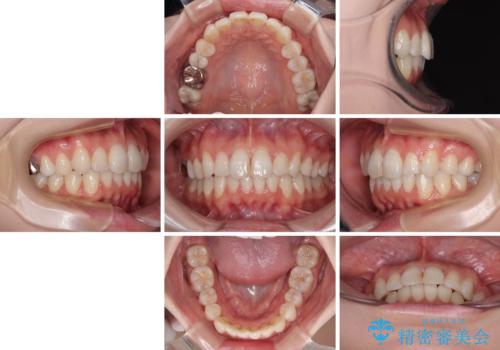

初めの1年くらいは何とか頑張って装着してくださいましたが、途中から変化をあまり感じられなくなり、日々の装着時間は徐々に短くなってしまいました。

前歯のデコボコはもっと改善できましたが、3年半が経過し、初診時と比べたら大幅に良くなったとのことで終了することとなりました。